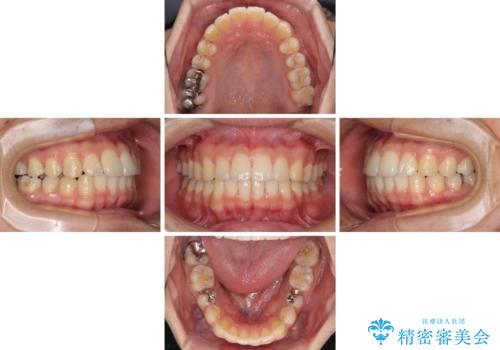

- 矯正治療の後戻りを気にして来院された患者様です。

後戻りは軽微でしたので、インビザライン・ライトにより矯正治療を行うこととしました。

再矯正後の後戻りを防ぐため、歯列排列後に、下顎前歯はワイヤーによる固定を行いました。

下顎前歯の歯列を動かないようにしておくことで、上顎前歯の後戻り防止にも効果を発揮します。